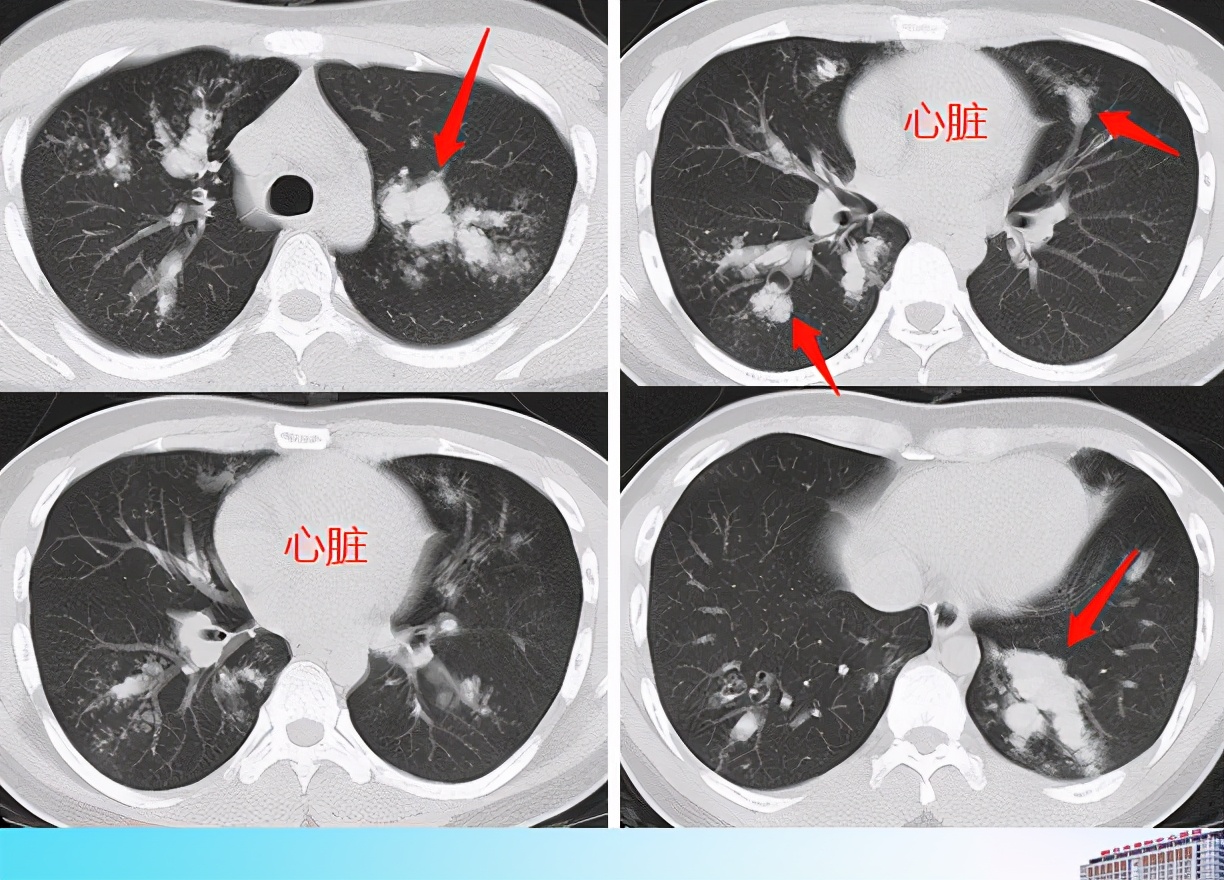

【影像读片】aip ards 重症肺炎 肺真菌病

图片尺寸3776x2520

病例肺部真菌感染毛霉菌肺炎1例ct影像表现